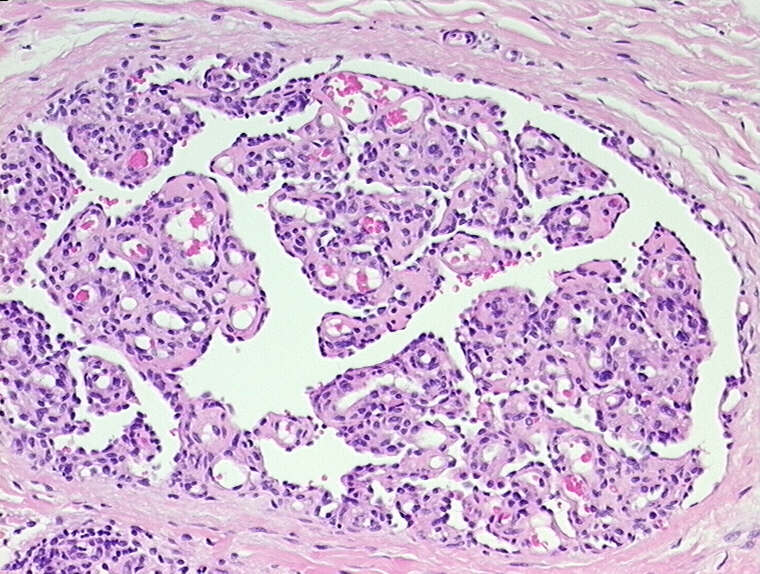

Glomeruloid hemangioma can be seen in healthy patients, but is also known to be associated with several conditions. List four disease associations.

*Image: dilated capillaries within a lumen, simulating the appearance of a renal glomerulus.